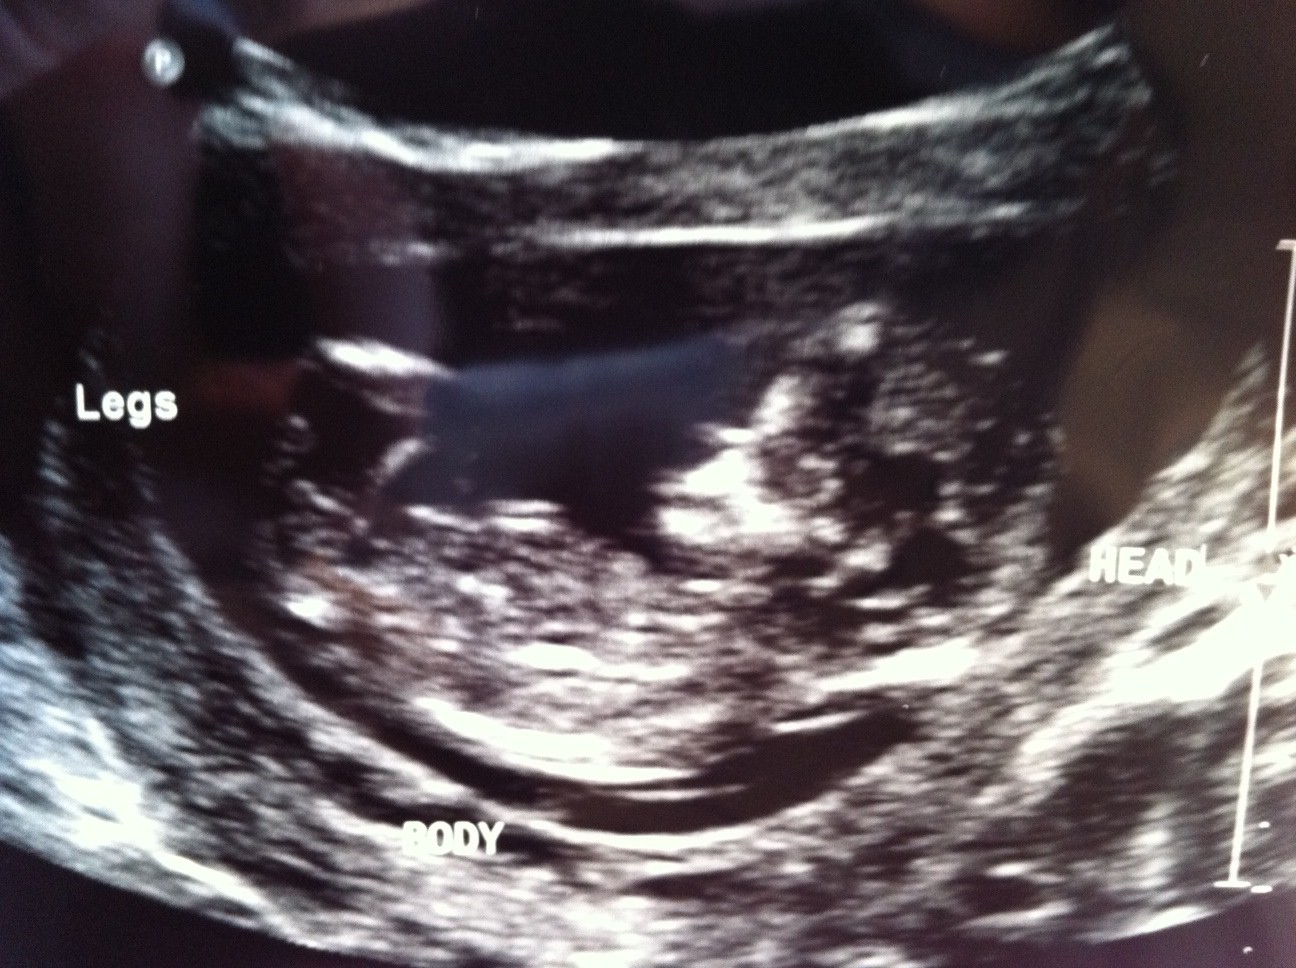

Sorry upside down.....Attachment 3520

Maybe not...that's a pretty big bulb at the end of the nub.

BOY!!!!! :D

What gestation exactly was this taken at? If around the 12 week mark I could see it going either way. If around 13 weeks, I would lean girl. Either way its not a totally clear nub that screams one or the other in my opinion.